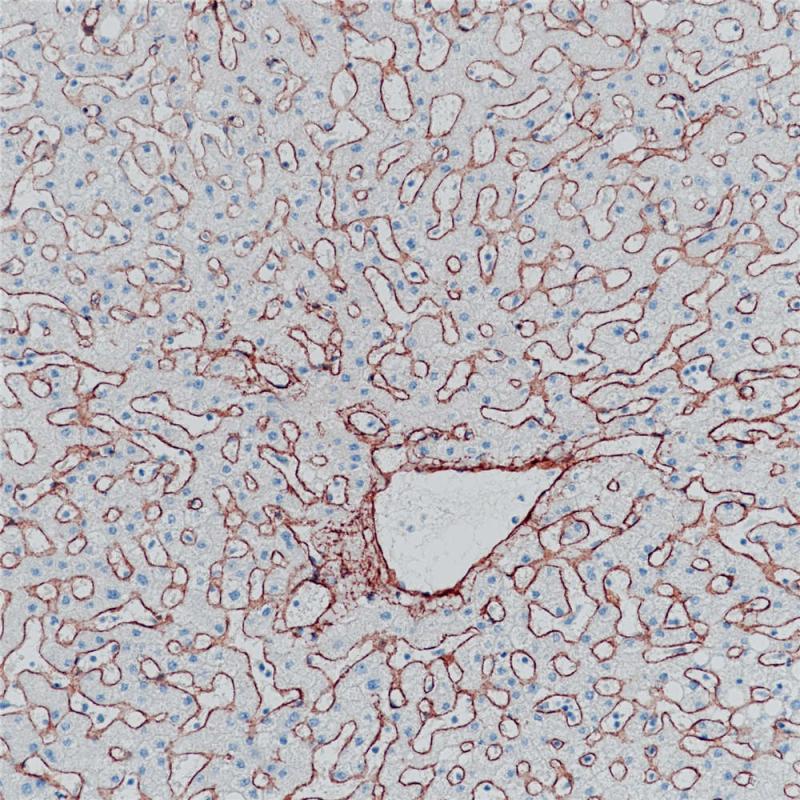

IV型胶原是基底膜的主要成分,与细胞粘附、转移、分化以及生长密切相关。IV型胶原在各类组织中均有表达,包括肾脏、肌肉、淋巴结、肺、肌腱和脾脏等。IV型胶原可用区分乳腺癌中的浸润癌和原位癌,在其他组织的良恶性研究也有报道,如胰腺癌、胰腺炎、肾脏疾病、口腔鳞癌、喉癌、卵巢癌、子宫内膜癌。